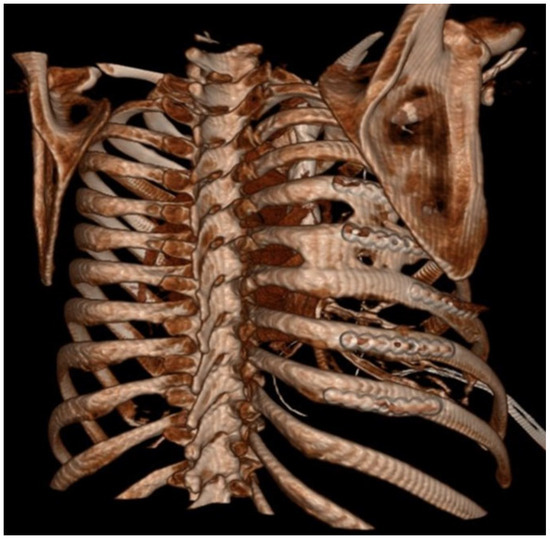

Figure 2. Three-dimentional reconstruction of CT scan with HO between ribs.

Patient-based variables were obtained from the medical records, including the following: age, race, gender, mechanism of injury, injury severity score (ISS), regional abbreviated injury severity score (AIS), medication administration, hospital length of stay, ICU length of stay, days of ventilator support, and discharge location. The existence of polytrauma was also evaluated, which was defined as any injury in a body region besides the chest with an AIS of 2 or greater. Rib fracture locations as well as displacement were characterized on initial CT scans based on their anatomical sector. These sectors consisted of the following: costal cartilage (CC); anterior (A) [rib costal cartilage junction to anterior axillary line]; lateral (L) [anterior axillary line–posterior axillary line]; posterior (P) [posterior axillary line to the lateral aspect of the paraspinus musculature]; and paraspinal (PS) [rib head–lateral aspect of the paraspinus muscles]. These anatomic divisions were used to further describe the location of SSRF titanium hardware on subsequent scans. All ribs were fixated using titanium plates with bicortical screw placement with a minimum of three screws anterior and posterior to the location of the fractures following the manufacturer’s guidelines. Both self-tapping (ST) and self-drilling (SD) screws were utilized as SD screws were not available until November 2019. ST screws require pre-drilling a bicortical osteotomy prior to placing the ST screw, which uses this pilot hole to guide its insertion into the rib. SD screws do not require this pilot hole to be drilled through the rib for fixation to occur. The number of plates used for fixation, as well as type of screws used for fixation, were recorded. Additionally, every patient undergoing SSRF underwent pleural space irrigation with 1 L of fluid and had a chest tube placed. Subcutaneous or submuscular drains were not used in any patients. All SSRF procedures were performed at a single center and by a single surgeon. Evidence of fracture healing and HO was also assessed using follow-up imaging evaluating the entire chest wall. The locations of the fractures as well as HO were characterized in the same manner as described above based on anatomic location. Non-union fractures were defined as a lack of cortical bone connection noted on follow-up CT scan axial cross-sectional imaging. HO was defined as calcium deposition in non-anatomic locations for bone (Figure 1 and Figure 2).

HO was noted in nine patients (43%) and seen as early as 8 months post-operatively. Overall, 15% (32/208) of rib fractures showed evidence of HO at follow-up. In patients that developed HO, 36% (32/88) of rib fractures had evidence of HO formation. The HO was evident on posterior–anterior chest X-ray in 25% (2/8) of patients. No significant difference was noted in patients with HO when accounting for gender (43.8% vs. 56.3%, p = 0.647), ISS (24 ± 12 vs. 18 ± 9, p = 0.265), flail chest injury (36.4% vs. 63.6%, p = 0.425), number of fractures (8 (4–16) vs. 9 (3–21) p = 0.917), polytrauma (44% vs. 50%, p = 0.801),time to follow-up CT scan (18.0 (7.7–88.5) vs. 14.2 (7.1–56.7) p = 0.247), or number of SSRF plates (4 (3–11) vs. 5 (3–11) p = 0.862). The number of patients with traumatic brain injury was similar, with three patients in both groups. A significant difference in these patients was identified when comparing approach to screw fixation pre-drilling with self-tapping (ST) screws versus self-drilling (SD) screws (89% vs. 11%, p = 0.024), year of operation (2107 ± 1.9 vs. 2020 ± 1.7, p = 0.004), and operative day (6 (0–9) vs. 2 (2–5), p = 0.023). All patients were treated with non-steroidal anti-inflammatory medications after injury (ibuprofen). The difference in patients with HO and the difference in types of screws used are illustrated in Figure 3.